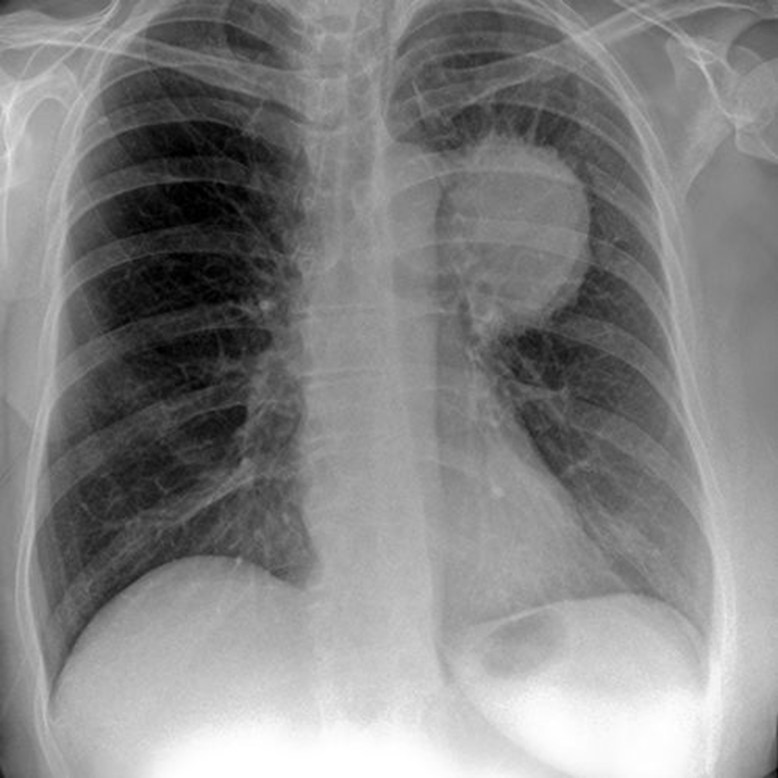

58 year old woman with this condition should stop taking these medicines.

What are NSAIDs?